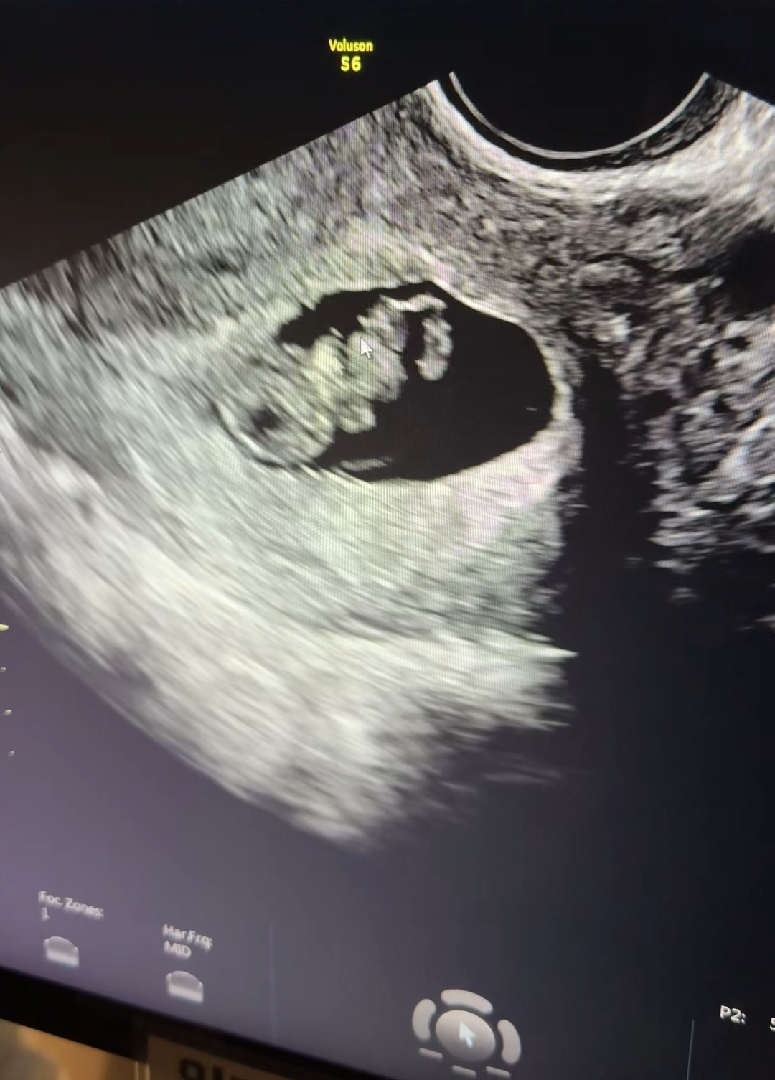

2주만에 갔는데 2등신 강낭콩에서 이제 머리몸통 팔다리 다 보이고 동영상에선 제가웃으니까 팔다리도 파닥거리더라구여ㅠㅠ 너무싱기하네요...!!! 너무기엽지않나요,,